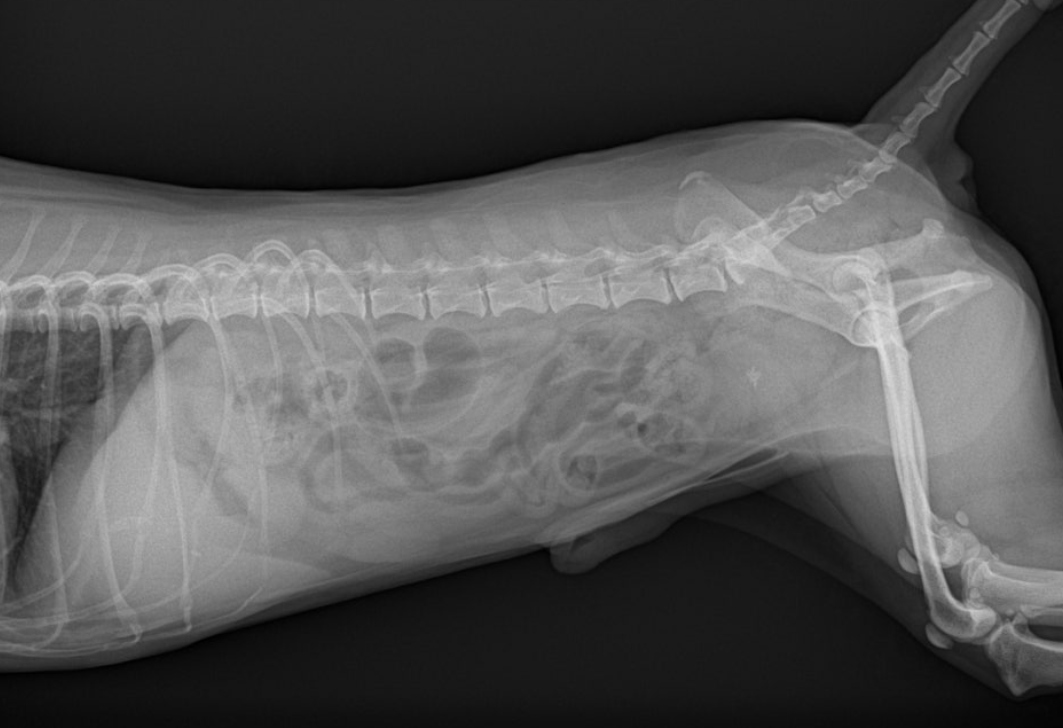

3️⃣ 방사선 검사(X-ray) 결석의 위치와 크기를 확인하는 기본 검사입니다.

대부분의 결석은 방사선에서 확인되지만, 종류에 따라 잘 보이지 않는 경우도 있습니다.

4️⃣ 초음파 검사

방광벽 두께, 염증 상태, 작은 결석 여부까지 확인할 수 있습니다.

요도 방향 이동 가능성도 함께 평가합니다.